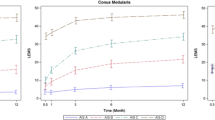

The time from injury to paralysis onset was classified as <30, 30–60, or >60 min. All SCIs were graded in accordance with the International Standards for Neurological Classification of Spinal Cord Injury [5]. All SCIs were verified by CT, X-ray, or MRI with a focus on abnormal signals indicating ischemia and hemorrhage. The involved segments of each patient on sagittal T2-weighted images (T2WIs) were accumulated to create a distribution map of the range of spinal cord edema and atrophy. All abnormal intramedullary signals of spinal cord lesions on axial T2WIs were classified in accordance with the Brain and Spinal Injury Center (BASIC) scoring system [6].

In the present study, the imaging data of 70 patients were collected and reviewed. For the other 18 patients, MRI data were not complete. No patient presented with a spinal fracture or dislocation on X-ray and CT images, although 67 patients had abnormal signals on T2WIs, which consisted of long T2 signals centering on the central canal of the spinal cord. The length of the long T2 signal was less than one vertebrae in two patients and more than one in 65. No patient had signs of significant hemorrhage on MRI (Fig. 3). Among these 67 patients, spinal cord edema most commonly involved the lower thoracic spine and lumbosacral medulla (Fig. 4). Of the 70 patients with imaging data, 45 had spinal cord atrophy, which was most commonly (40 patients) concentrated between T8 and the conus medullaris. Of these 45 patients, 30 (66.7%) developed atrophy within 90 days, including 4(8.9%) within 1 month, and 15 (33.3%) at more than 90 days. As to analysis of axial T2WIs, three patients had a BASIC score of 0, seven had a BASIC score of 1, 57 had a BASIC score of 2, three had a BASIC score of 3, and none had a BASIC score of 4 (Fig. 5).

A review of the MRI data of 70 patients found that the main abnormality in the first week after SCI was a long T2 signal around the center of the spinal cord, accompanied by swelling. In addition, sagittal images of 65 patients showed long T2W signals involving more than three vertebrae, most of which were located from T8–10 to the conus medullary, which sometimes included another long signal of the upper thoracic spine, mostly involving the T3–5 vertebrae corresponding to a poor blood supply. Two studies conducted by Bolton [17] and Zülch [18] pointed out that T4 and L1 were sensitive to ischemia, while Dommisse [19] found that the spinal canal is narrowest between T4 and T9, which results in an inadequate blood supply. Moreover, a 2013 imaging study conducted by Nakamoto et al. [20] of 23 patients with surfer’s myelopathy described “pencil-like” long T2 signals from the midthoracic spinal cord (T5–10) to the conus medullary. The abnormal range involved three to seven and a half vertebrae, which was accompanied by enlargement of the conus medullary, similar to the patients in the present study. More importantly, the late stage of ischemia was characterized by spinal cord atrophy. In the present study, spinal cord atrophy below the site of injury was found in 45 patients (64.3%) at more than 3 months after the injury. The levels of spinal cord edema during the early stage of injury and subsequent atrophy were concentrated between T8 and T10, which was the area of the spinal cord with a poor blood supply.